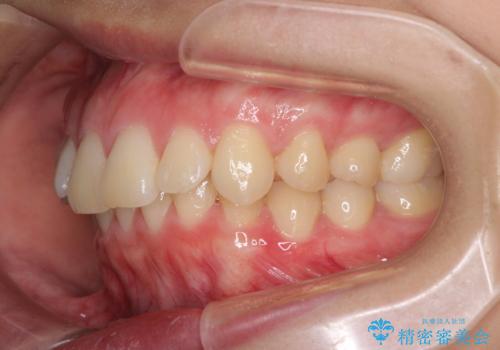

上顎前突 目立たないワイヤー装置での抜歯矯正

左右ともに下顎に対して上顎歯列が前方位にある上顎前突であったので、上顎歯列全体を後方に移動させることで上下咬み合わせを改善し、その上で抜歯矯正により口元の突出感を改善させていきました。

- 口元の突出感改善を希望して来院された患者様です。